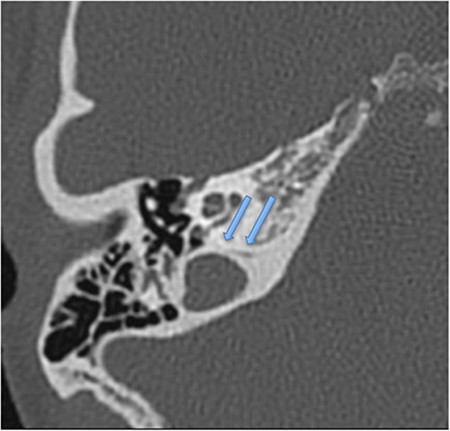

A 26-year-old woman, primigravida and primipara, was admitted to the institution with spontaneous labour at full term. Emergency caesarean section was deemed necessary due to a prolonged latent phase of labour and foetal distress concerns as seen on cardiotocography. The patient was placed in an appropriate position for skin preparation with chlorhexidine, and then local infiltration was performed using 3 ml of 2% lidocaine. An 18-guage needle was used for the epidural catheter placement, and loss of resistance technique was used to identify the epidural space. The needle was inserted 5.5 cm cephalad into the epidural space at L3–4 by the midline approach. Then 12 ml of 0.2% ropivacaine and 16 micrograms of fentanyl was injected, followed by a ropivacaine and fentanyl infusion. Surgery was completed within 45 minutes, and no intraoperative complications transpired. Haemodynamic parameters remained normal throughout the perioperative period. The epidural catheter was removed within 12 hours postoperatively, with no complications. Day 1 postoperatively, the patient reported a sensation of light-headedness and dizziness but no headache. Day 2 postoperatively, she was discharged at home. No ototoxic medications were administered during admission or dispensed on discharge. On the same day, the patient noticed a constant right ear hearing loss, ongoing unbalance, a sensation of aural fullness and high-pitched non-pulsatile tinnitus. She attended her local primary care physician the same day and was treated with intranasal corticosteroids for possible eustachian tube dysfunction. Persistence of symptoms for 2 weeks prompted an audiological assessment which diagnosed a SNHL (Fig. 1). Urgent ENT specialist advice was sought over the phone, and the patient was commenced on systemic corticosteroids for 7 days (1 mg/kg of prednisone). The patient has no previous ear symptoms, no prior ear surgery, trauma or recent upper respiratory tract infection. A posterior fossa magnetic resonance imaging scan was performed but found no pathology. High-resolution temporal bone computed tomography (CT) scan demonstrated an enlarged right cochlear aqueduct (Fig. 2). Repeat audiological assessment in 2 weeks showed no pure tone audiometry change, but significant improvement in speech discrimination was present (53–90%). The patient was then seen in a specialist ENT clinic. Physical examination including microscopic otoscopy was unremarkable. Unilateral hearing loss management options were discussed with the patient, with conventional hearing amplification recommended. Repeat audiogram at 4 and 10 months’ time showed no further improvement but stabilised hearing. The patient has declined the use of amplification, and a recommendation to avoid further spinal-epidural anaesthesia was given.